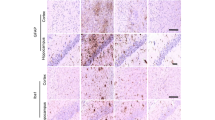

LPS markedly increased the expression levels of COX-2 and iNOS, while LC (10, 5, and 2.5 µM) attenuated this effect (Fig. 6A–C). Immunofluorescence analysis was performed to further explore the effect of LC on the nuclear migration of the important inflammation-related protein NF-κB p65, and LC relieved the increased intensity of pink fluorescence induced by 1 µg/mL LPS. Thus, the experimental results demonstrate that LC can decrease the protein levels of proinflammatory mediators.

LC inhibited the expression of several inflammatory proteins in LPS-induced BV-2 cells. A Expression levels of COX-2 and iNOS. B, C COX-2 and iNOS band densities were quantified after normalization to the control band density. D Immunofluorescence results of NF-κB-P65. Data are expressed as the mean ± SEM (n = 3). Differences were evaluated by one-way ANOVA or Student’s t test. The significance level was set at 0.05. ####p < 0.0001 vs. the control group. *p < 0.05, **p < 0.01, ***p < 0.001, ****p < 0.0001 vs. the LPS group. β

The NLRP3 inflammasome pathway plays a vital role in inflammatory signaling pathways. The protein expression levels of NLRP3, Caspase-1, and ASC in BV-2 cells were measured by western blotting. LPS significantly increased the protein expression of NLRP3, ASC, and Caspase-1 (Fig. 7A–D). LC decreased the protein expression of NLRP3, ASC, and Caspase-1; however, regarding ASC and Caspase-1 expression, the effect was not concentration-dependent. Immunofluorescence analysis demonstrated that the LPS-treated cells were positive for NLRP3 (pink) in the cytoplasm, whereas control cells were not (Fig. 7F). NLRP3 expression was considerably lower in the LC-treated groups than in the LPS group. These results indicate that LC inhibits the inflammatory response, partly via the NLRP3-mediated inflammasome.

LC inhibited the activation of the NLRP3 inflammasome. A Expression levels of NLRP3, ASC, and Caspase-1. B–D NLRP3, ASC, and Caspase-1 band densities were quantified after normalization to the control band density. E The virtual docking model of LC with NLRP3. F Immunofluorescence results of NLRP3. Data are expressed as the mean ± SEM (n = 3). Differences were evaluated by one-way ANOVA or Student’s t test. The significance level was set at 0.05. ###p < 0.001, #p < 0.05 vs. the control group. **p < 0.01, *p < 0.05 vs. the LPS group

Microglia are CNS immune cells that can protect neurons by phagocytosing pathogens and harmful particles in the brain tissue and can also activate reactive microglia that secrete inflammatory cytokines in response to inflammatory factors, resulting in neuronal toxicity [28, 29]. Therefore, reactive microglia are an important target for treating neuroinflammation and NDs [30]. LPS, a glycolipid composed of lipids and polysaccharides, is a constituent of the outer wall of gram-negative bacterial cell walls [31, 32]. LPS-induced microglial activation results in a series of inflammatory responses, such as the production of multiple proinflammatory mediators (ROS, RNS, PGE2, NO, iNOS, and COX-2) and cytokines (TNF-α, IL-6, and IL-1β), that further deteriorate neurons [33]. Damaged neurons produce many ROS, which activate microglia, thus forming a vicious cycle [34]. The NF-κB signal transduction pathway plays an important role in the inflammatory response [35,36,37]. Normally, IκB is confined to the cytoplasm when not activated and undergoes phosphorylation upon LPS stimulation. NF-κB is isolated from the IκB complex and continuously activated, translocating from the cytoplasm to the nucleus and binding to target gene promoters to activate transcription, leading to the synthesis and secretion of NO, TNF-α, and IL-6, generating inflammation [38]. LC can dramatically suppress NO generation as effectively as the positive medicine dexamethasone in BV-2 cells, preliminarily demonstrating its anti-neuroinflammatory function. RT-PCR, immunofluorescence, and western blotting techniques were applied to further explore LC’s mechanisms of action. LC was found to play an anti-inflammatory role by suppressing the NF-κB p65 signaling pathway and inhibiting the expression of cytokines, such as TNF-α, IL-1β, and IL-6, and several significant inflammatory factors, such as COX-2 and iNOS (Fig. 6). The activation of the NF-κB-P65/IκB pathway is often accompanied by the nuclear entry of NF-κB p65. Therefore, we performed immunofluorescence analysis to verify that LC could indeed inhibit the nuclear entry of NF-κB p65. This result was further confirmed by western blotting.

The NLRP3 inflammasome plays a significant role in neuroinflammation. This study demonstrated by immunofluorescence analysis that LC can indeed inhibit the activation of the NLRP3 inflammasome, and the results were further confirmed by western blotting. The NPAI Engine system was used to perform molecular docking between LC and NLRP3. The docking results also showed that LC closely binds to NLRP3 through hydrogen bonding, conjugation, hydrophobic interactions, and other intermolecular forces. Therefore, the natural product LC is highly likely to protect neuronal cells by inhibiting the activation of the NLRP3 inflammasome. Regarding the antioxidant mechanism of LC, we also found that different concentrations of LC could significantly increase the expression level of HO-1 in BV-2 cells, indicating potent antioxidant action.